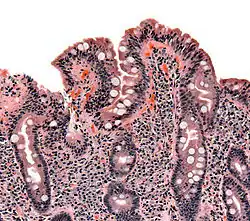

Biopsi af tyndtarmen som viser tegn på cøliaki

Ved cøliaki ødelægges slimhindentyndtarmens inderside, så den efterhånden bliver glat og uden de normale villi (fimrehår). Fordøjelsen og optagelsen af vigtige næringsstoffer nedsættes i større eller mindre grad, alt efter hvor fremskreden ødelæggelsen af tarmen er.

Den endelige diagnose stilles traditionelt ved en biopsi af tarmslimhinden. Undersøgelse af prøven under mikroskop kan påvise større eller mindre ødelæggelse af tarmslimhinden. Prøven skal tages efter en længere periode med rigeligt glutenindhold i kosten, da prøverne ellers kan være falsk negative.